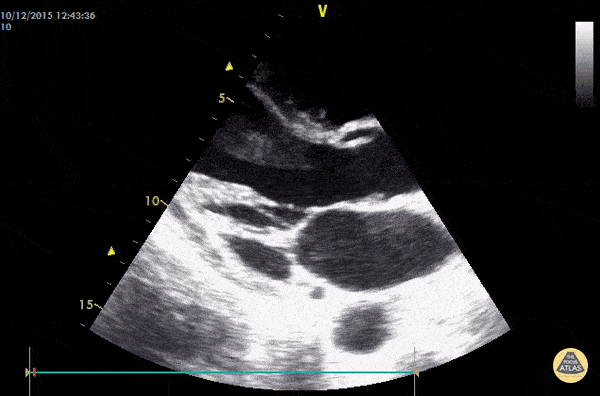

Vegetations on the AV valve (endocarditis). 40y old female coming to the ED with acute ischemia of the left lower limb and fever. IVDA. Dr. Dominik Doeller